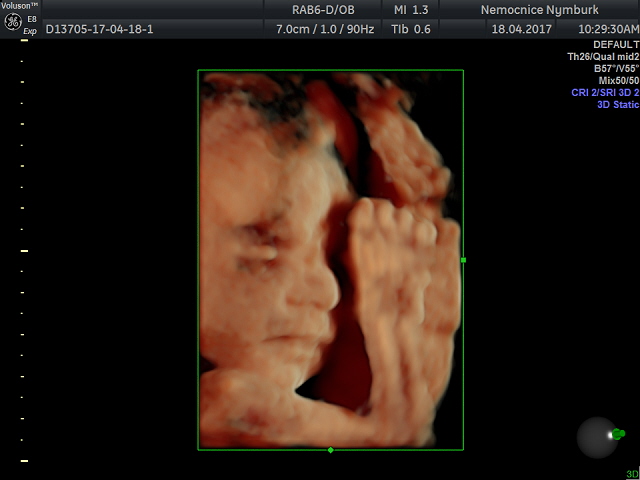

Ahoj všem, tak dnes mám po další kontrole 28+4 a vše odpovídá :-) maličká je v pořádku, je to pořád holka a dneska se i chtěla ukazovat :-) vyplazovala na nás dokonce i jazyk :-) má 1323g, zatím je položená zadečkem dole, ale prý je ještě spousty času aby se otočila. Doktor se divil, že na svou váhu mám super výsledky z cukrovky, že se to moc nestává, čípek zavřený, otoky nikde. Příští týden jdu ještě k obvoďákovi na ekg a pak ještě jednou zubař a kolečko mám snad kompletní - hurááá!

Slonice krásná fotka, koukám, že jsem se ani tím našim raráškem nepochlubilaLaughing monitor dechu jsem měla u dcerky a chci ho znovu, lépe se mi spí, teda já byla u dcery tak vyfluslá, že jsem spala i ve stoje u kočárkuLaughing zubaře jsem nějak podcenila, jdu zítra, hold budu mít jen jedno razítko a ještě se objednat k obvoďákovi. Teď řeším MD, protože mi končí doma určitá v červnu, tak to bude pro SSSZ oříšek vzhledem k dlouho neschopence, snad dostanu možnost vybrat si RD na 3 roky, uvidíme.